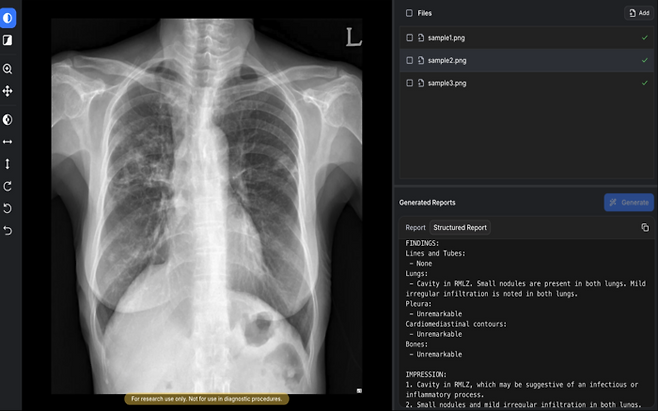

의료 인공지능 기업 숨빗AI가 자사의 흉부X선 예비소견서 생성 솔루션 'AIRead-CXR'(에어리드-씨엑스알)에 대해 대한민국 식품의약품안전처(MFDS) 3등급 인허가를 획득했다고 2일 밝혔다.

AIRead-CXR은 의료영상 분야에서 세계 최초로 생성형 AI 기반 소프트웨어 의료기기(SaMD)로 MFDS 허가를 받은 제품이다. 기존에 유럽에서 생성형 AI 기반 의료기기가 존재하지만, 의료영상을 직접 분석해 예비소견서를 생성하는 단독 제품으로는 이번 승인이 처음이라는 점에서 의미가 크다.

AIRead-CXR은 국내외에서 확보한 약 1400만건의 데이터를 학습해, 다양한 병원 환경에서 촬영된 PA 또는 AP 흉부X선에 대해 안정적으로 예비소견서를 제공한다. 핵심적으로 검증된 57개 소견 및 질환에 대해 높은 수준의 판독보조 성능을 제공할 뿐 아니라, 이 외의 다양한 영상 소견도 해석·언급할 수 있다. 실제 임상 현장의 워크플로우를 반영해 의료진이 보다 효율적으로 판독 업무를 수행할 수 있도록 설계됐다.

품질 경쟁력도 주목된다. 공개된 임상논문에 따르면, 흉부영상 전문의들이 평가한 AI 예비소견서 평균 수용도는 85%로, 비교 대상인 MedGemma(66.9%)를 상회했다. 생성형 AI의 대표적 한계인 환각 비율 역시 0.3%로, MedGemma(9.7%) 대비 우수한 안정성을 보였다. 이러한 기술력과 임상적 유효성은 영상의학 분야 최고 권위 학술지인 래디올로지(Radiology)에 3편, AJR에 1편 이상의 논문으로 뒷받침되고 있다.